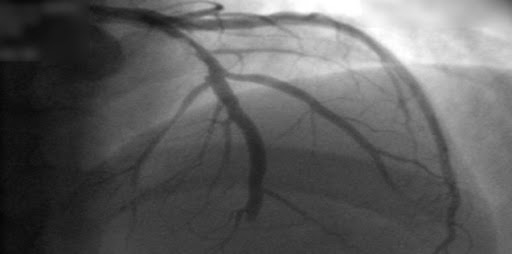

Intervención coronaria percutánea en angina crónica estable: un ensayo clínico doble ciego

En pacientes con angina estable que recibían poca o ninguna medicación antianginosa y tenían evidencia objetiva de isquemia, la intervención coronaria percutánea resultó en una puntuación de síntomas de angina más baja (una media de 2,7 puntos menos en una escala de 79 puntos) que un procedimiento con placebo, lo que indica un mejor estado de salud con respecto a la angina. New England Journal of Medicine, 21 de diciembre de 2023.